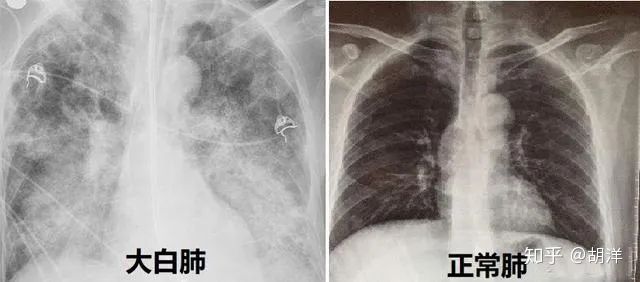

清肺排毒汤组方:麻黄9g、炙甘草6g、杏仁9g、生石膏15~30g(先煎)、桂枝9g、泽泻9g、猪苓9g、白术9g、茯苓15g、柴胡16g、黄芩6g、姜半夏9g、生姜9g、紫菀9g、冬花9g、射干9g、细辛6g、山药12g、枳实6g、陈皮6g、藿香9g。水煎服,每日一副,早晚两次,饭后40分钟温服,三副一个疗程。如有条件,每次服完药可加服大米汤半碗,舌干津液亏虚者可多服至一碗。(注:如患者不发热则生石膏的用量要小,发热或壮热可加大生石膏用量)。若症状好转而未痊愈则服用第二个疗程,若患者有特殊情况或其他基础病,第二疗程可以根据实际情况修改处方,症状消失则停药。临床用于新型冠状病毒感染的肺炎轻型、普通型和重型患者的救治。这是一张合方,有21味药,由麻黄汤、射干麻黄汤、麻杏石甘汤、小柴胡汤、五苓散五个经方合并加减而成,符合合方治大病的经方治病原则。由此可见,拟方人葛又文不愧为治疗伤寒的高手。全方针对的是新冠肺炎虚实、寒热和湿毒,扶正与祛邪共施、辛温与辛凉、清热与燥湿、解毒与利水并用。其功效为宣肺平喘、解毒化湿。新冠肺炎发病病机被有关中医专家一致认定为“寒湿疫”,也就是说,新冠肺炎是由于体内寒湿过重而被病毒传染的。脾恶湿,整个方剂重点在于太阴经化湿,也就是瞄准的是疾病的本源,旨在通过温化寒湿,改善体内的寒湿环境,让病毒无法生存,从而达到“正气存内,邪不可干”的目的。脾属足太阴经,肺属手太阴经。这两个经是相生关系,脾的运化水谷能力与否,直接影响着肺的宣发肃降。脾本来是运化水谷精微,滋养五脏六腑,如果运化无力,水谷精微就会变成水饮,从而形成痰湿。痰湿形成之后,又会阻碍脾的运化功能。这就是“脾为生痰之源”的根源。脾生的痰要储藏到肺里,“肺为储痰之器”,肺司呼吸,痰浊壅滞肺络,气道受阻,就会出现喘息咳唾,症状加重则引发呼吸困难。肺被痰湿壅塞,病情就会进一步加重,出现胸闷憋气,痰多难咯,医生只好让患者进入ICU救治。由于有痰浊太多,氧气无法被肺吸收,所以血氧值一直上不去,最后患者被痰浊活活憋死。尸体解剖后发现肺里充满了白色胶粘物,这些白色胶粘物就是“白肺”。一旦出现“白肺”,当务之急就是清理痰湿。如果用清热药或抗病毒药物,会使寒湿逐渐加重,就更不好治了。放开以来,令人没有想到的两个严重问题,一个是,没放开前很少有阳的,少数阳的隔离一下就没事了。放开后,如同“千树万树梨花开”,呼啦一下全国都阳了,中邪了一般。二是由于专家一直在叨叨奥密克戎就是大号流感,症状比感冒还轻,国家更名为“新型冠状病毒感染”。可是,谁都没有想到,这个“轻症”,仅咳嗽和嗓子痛,把人折磨得痛苦不堪,更为严重的是居然爆发了随时夺走患者性命的“大白肺”。从报道看,有不少老人感染奥密克戎,很快就去世了,快的连送医院都来不及。说老人大多合并基础病不易治疗,可怕的是有的年轻人也被检查出“大白肺”。专家说过,尽管新冠肺炎后病毒发生了变异,如“阿尔法”、“德尔塔”以及现在的“奥密克戎”,但是,其病机“寒湿疫”一直没有变。2020年对新冠肺炎尸检发现“白肺”是“肺里充满了白色胶粘物”,目前的“大白肺”也是肺里被“黏稠分泌物”阻塞。可见,“白肺”和“大白肺”完全是一种病,只是病名上加了一个“大”字而已。2020年,新冠肺炎重症患者的“白肺”,最终基本全被清肺排毒汤治愈,所以,面对现在令人恐怖的“大白肺”,只要使用清肺排毒汤也应该可以自愈。遗憾的是,疫情放开之后,阳的人这么多,因为“大白肺”夺走了那么多生命,中医治疗的声音一点都没有,治疗新冠肺炎的特效药“清肺排毒汤”居然连中医专家都不提了,这是为什么?放着廉价、高效,能救命的特效药不用,却舍近求远进口含有诸多副作用的昂贵西药,不知某些人心里打得什么算盘?这么好的救命药,全国4000多家制药厂竟然没有大批生产,眼巴巴看着百姓无药可用,看着危重患者无药可治。有海外网友反馈,“清肺排毒汤”已经有国内企业在生产,但只能在美国买到,我国没有销售。在美国销售的“清肺排毒汤”是由桂林葛仙翁药业有限公司生产的,袋装包装,一袋里有15小袋,一袋13.99美元。